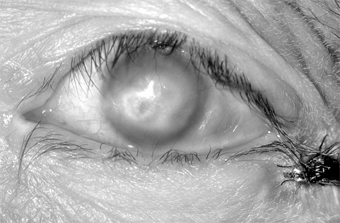

In adults, the conjunctiva of both tarsi-especially the lower tarsus-have papillae and follicles (Figure 5-3). Since pseudomembranes do not usually form in the adult, scarring does not usually occur. Superficial keratitis may be noted superiorly and, less often, a small superior micropannus (< 1-2 mm). Subepithelial opacities, usually marginal, often develop. Otitis media may occur as a result of infection of the auditory tube.

Figure 5-3

Figure 5-3: Acute follicular conjunctivitis caused by inclusion conjunctivitis in a 22-year-old man with urethritis. (Courtesy of K Tabbara.)